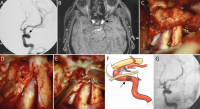

Neurovaskuläre Therapieoptionen bei komplexen Aneurysmen der Arteria carotis interna // Neurovascular therapeutic options in complex intracranial aneurysms

Journal für Neurologie, Neurochirurgie und Psychiatrie 2021; 22 (3): 128-134 Volltext (PDF) Summary Praxisrelevanz Abbildungen